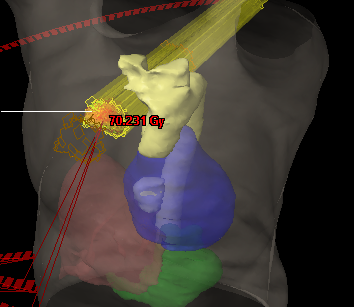

Over his career, Professor Armstrong has authored numerous peer-reviewed publications, lectured extensively, and mentored emerging clinicians and researchers. He has been instrumental in the enrolment of over 2,080 patients into clinical trials at SLRON—a significant national milestone. He currently leads the 18-33 Source Trial, a pioneering investigator-initiated study focused on advanced radiation techniques, which IRROG is supporting for national rollout.